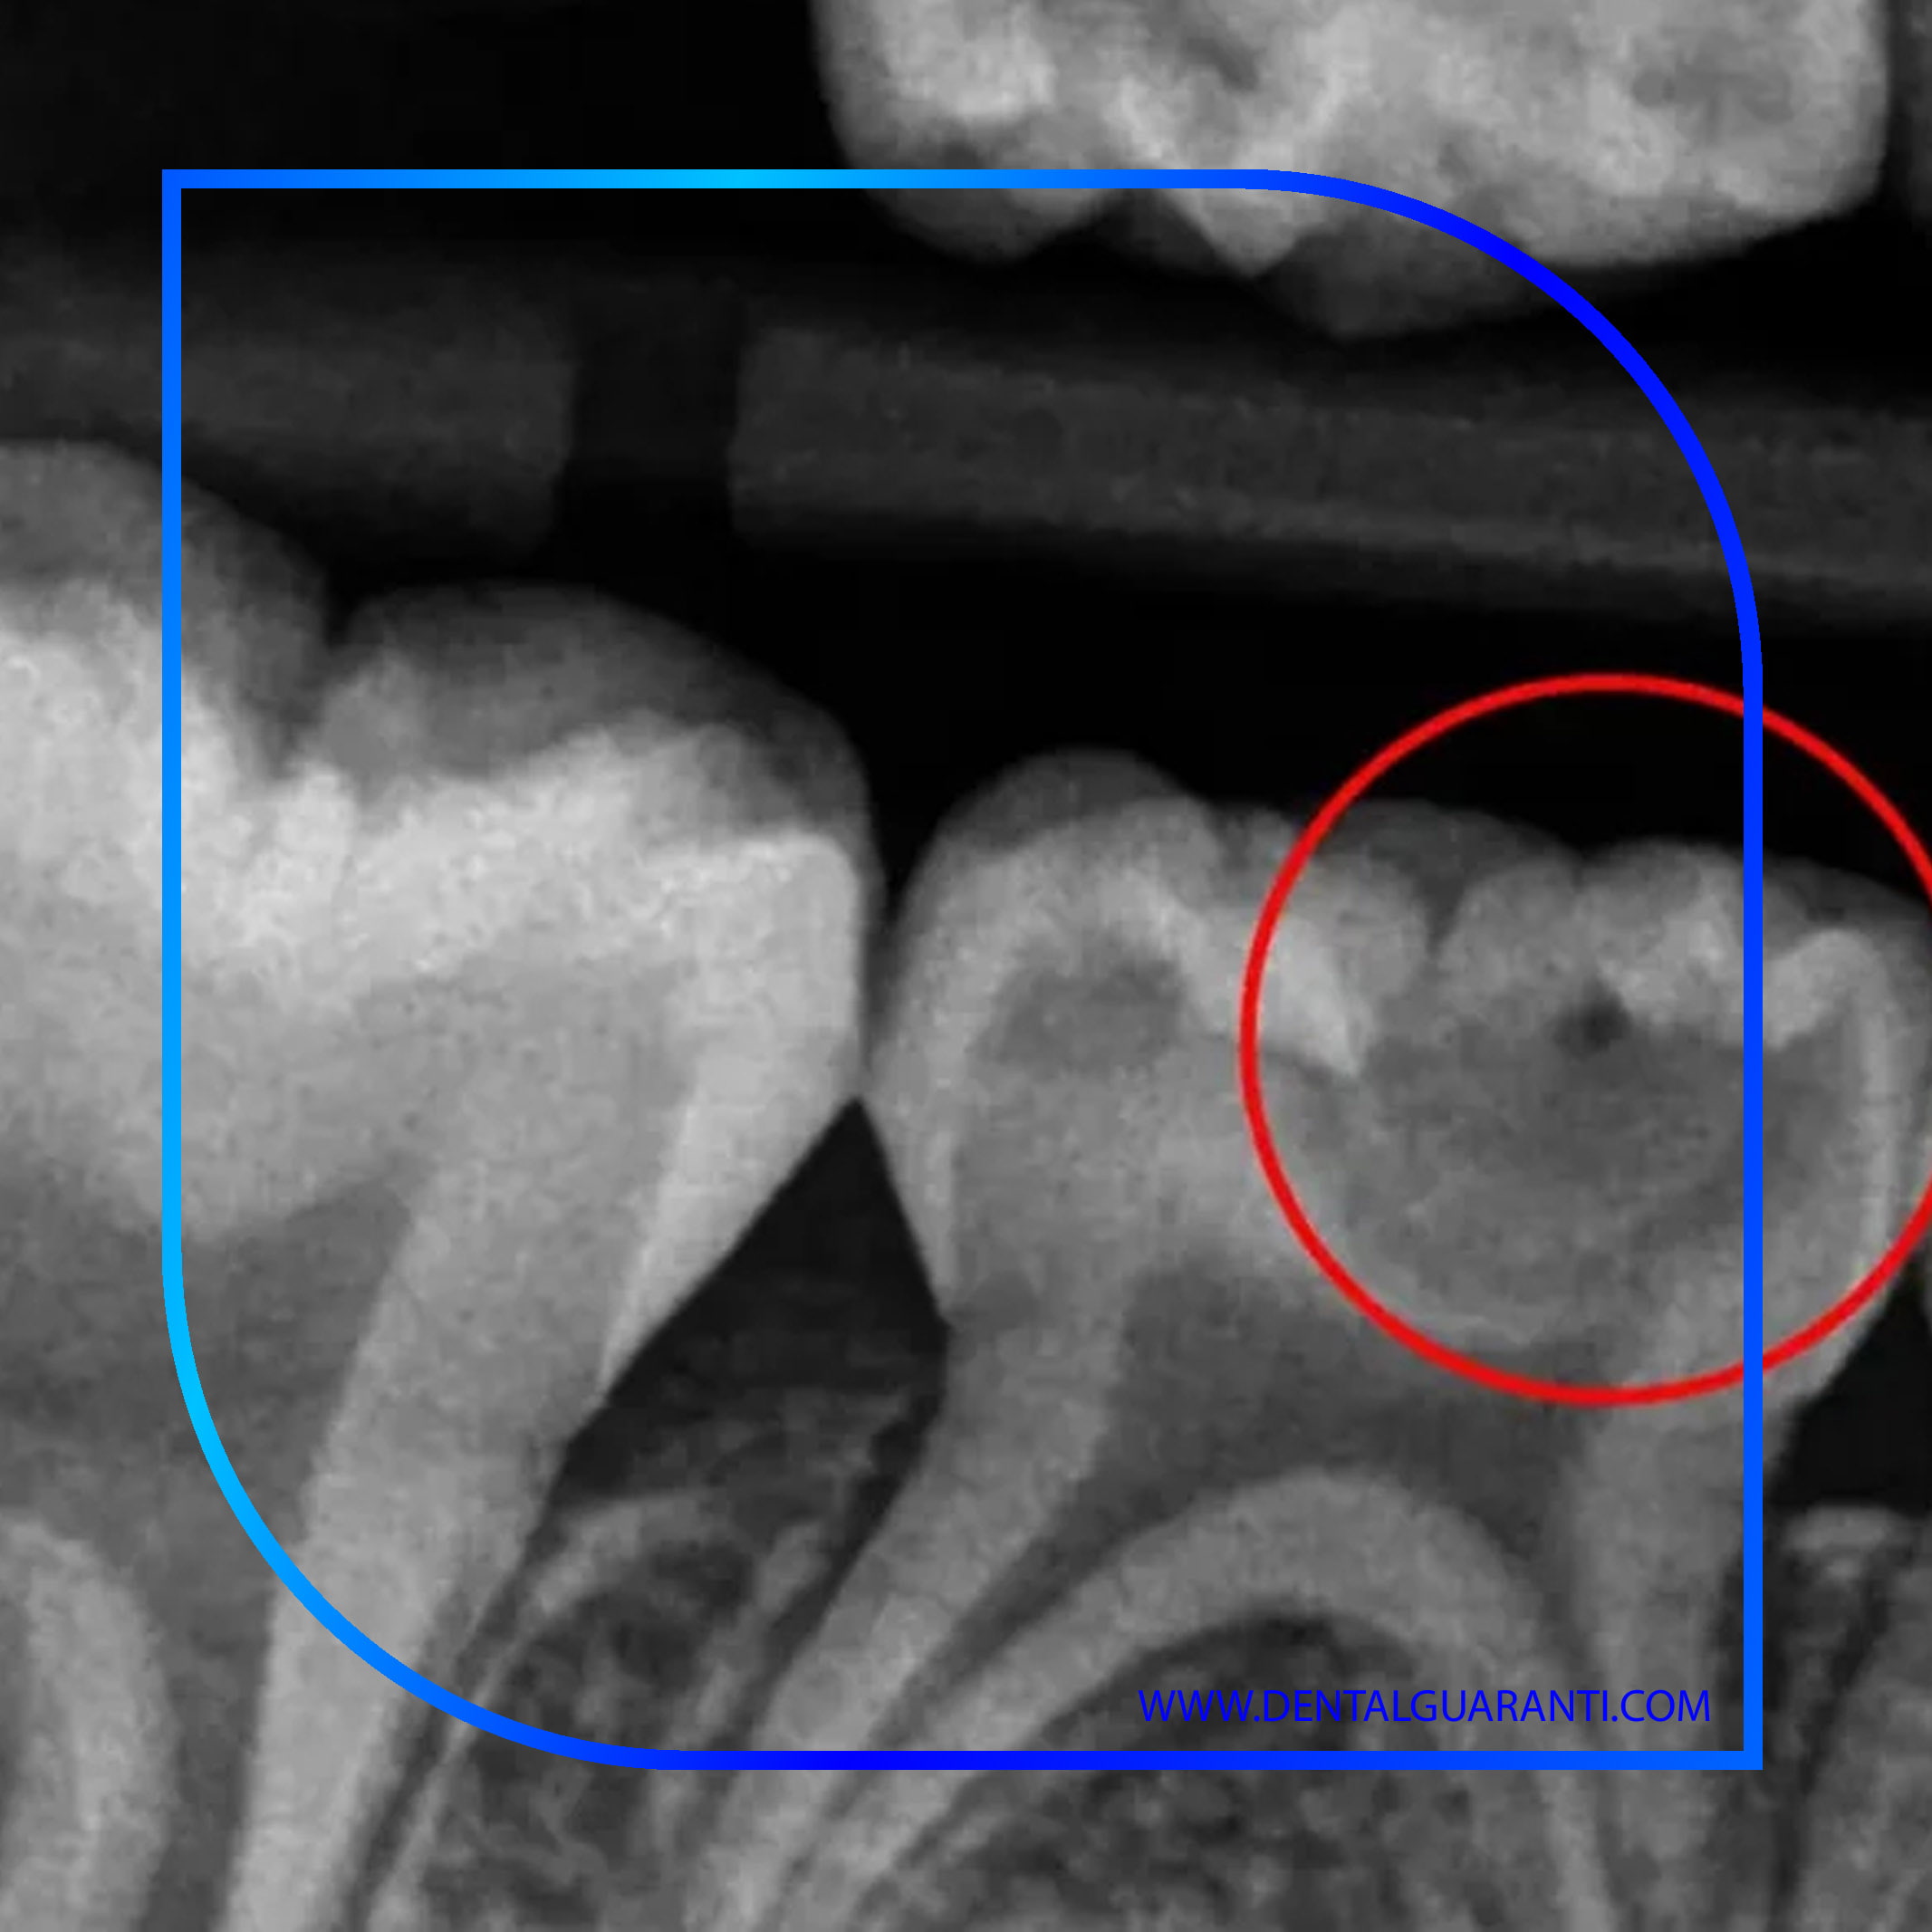

یکی از مهمترین گامها در تکامل روشهای تشخیص، جایگزینی رادیوگرافیهای سنتی با فناوریهای دیجیتال و سهبعدی است. تصویربرداری دیجیتال نهتنها دوز اشعه را به میزان چشمگیری کاهش داده، بلکه وضوح و دقت تشخیص را افزایش داده است. در این فناوری، تصاویر دندانها بهصورت آنی روی مانیتور نمایش داده میشوند و دندانپزشک میتواند با بزرگنمایی یا تغییر کنتراست تصویر، کوچکترین نشانههای پوسیدگی دندان را مشاهده کند.

در سیستمهای پیشرفتهتر مانند CBCT (Cone Beam CT) و Digital Radiography، امکان مشاهدهی ساختار داخلی دندان در سه بُعد فراهم است. این ویژگی در تشخیص اولیه پوسیدگیهای بیندندانی یا زیر لایهی مینا اهمیت حیاتی دارد، زیرا این نواحی معمولاً در تصاویر دوبعدی قابل تشخیص نیستند.